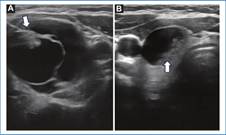

Con respecto al tamaño, los NT inferiores a 14 mm fueron los más comúnmente observados. Las microcalcificaciones estuvieron presentes en el 12,9% de los casos (Fig. 6) y las macrocalcificaciones en el 13,8% de los NT. Se reportaron ganglios anormales asociados hasta en el 9,2% de los casos. La información de las características ecográficas comparando NT benignos y malignos se presentan en la tabla 2.

El consenso de la Sociedad de Radiología en Ecografía para el manejo de NT y la Sociedad Americana de Endocrinología Clínica recomienda la realización de BACAF para nódulos mayores a 10 mm29,30. Aunque la BACAF es una técnica segura, sus tasas de resultado diagnóstico son variables en la literatura (0,4-40,7%)31. En nuestro estudio tuvimos un total de 94 biopsias no diagnósticas (29,1%). Consideramos como posibles causas los tamaños del NT biopsiados con resultado insatisfactorio, que en nuestro trabajo tuvo un promedio de 11,57 mm y la composición quística de algunos NT. Dos estudios publicados por Baier y Grani reportan como causa de resultados no diagnósticos el tamaño del nódulo < 10 mm, la dominancia quística (Fig. 8) y la edad del paciente mayor a 75 años32,33. Es importante mencionar que aunque la literatura no recomiende la biopsia para lesiones menores a 10 mm, es necesario realizar seguimiento ecográfico o considerar la biopsia junto a un equipo multidisciplinario experto, dado que el 71% de los NT malignos detectados en nuestro estudio se encontraban en el grupo de tamaño inferior a 14 mm y el 34% de los NT fueron inferiores a 10 mm.